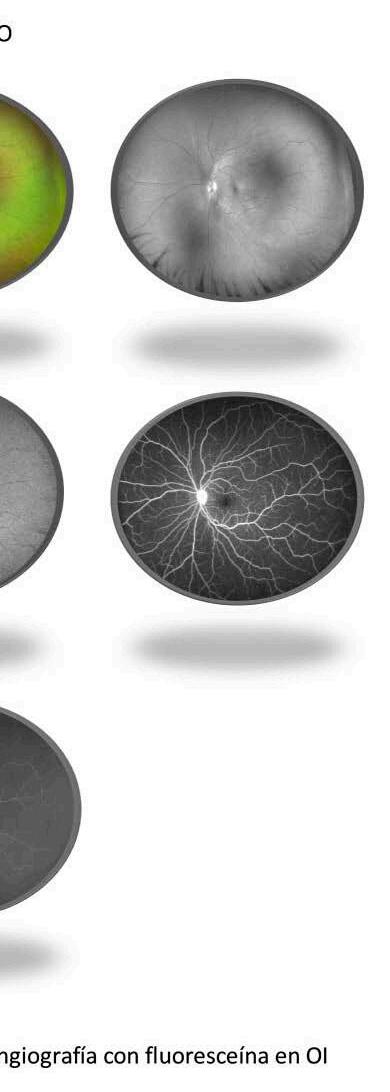

Se realizaron estudios de imágenes. La tomografía de coherencia óptica (OCT) macular del OD ( Figura 1.A. ) evidenció desprendimiento del neuroepitelio subfoveal; en el OI ( Figura 1.B. ), se observó una disminución de la depresión foveal. El OCT papilar ( Figura 2. ) reveló un aumento del grosor de la capa de fibras nerviosas, más marcado en el OD ( Figura 2.A. ). La angiografía con fluoresceína (AGD) ( Figura 3.A. y 3.B. ) demostró desprendimientos lobulados en el polo posterior del OD (tanto en el sector nasal como temporal), y un patrón multifocal de puntos hiperfluorescentes (“pintpoint”) en AO, con hiperfluorescencia papilar en fases tardías, más intensa en el OD. La autofluorescencia mostró áreas focales de fluido subretinal.

Panuveitis bilateral por síndrome de Vogt-Koyanagi-Harada en paciente pediátrica.

costeroides orales (Deltisona B, 1 mg/kg/día), observándose a los 12 días una mejoría significativa de la AV (OD: 5.5/10, OI: 9/10), disminución del Tyndall y de la hiperemia en la biomicroscopía, y resolución del líquido subretinal en el OCT de control ( Figura 4 ).

Los estudios multimodales, como la OCT, la angiografía con fluoresceína (AGD), desempeñaron un rol clave en la confirmación diagnóstica. Hallazgos como el desprendimiento subfoveal del neuroepitelio, el engrosamiento de la capa de fibras nerviosas y el patrón multifocal de hiperfluorescencias puntiformes (“pinpoint”) son característicos de la fase aguda de VKH 8,9

La utilización oportuna de estudios como la OCT y la angiografía con fluoresceína (AGD) resultó crucial para el diagnóstico y el seguimiento terapéutico. La respuesta favorable al tratamiento con corticosteroides orales en esta paciente refuerza la importancia del abordaje precoz para evitar complicaciones visuales irreversibles. No obstante, el seguimiento a largo plazo es fundamental para detectar recaídas o progresión a formas crónicas, que son más frecuentes en la edad pediátrica.